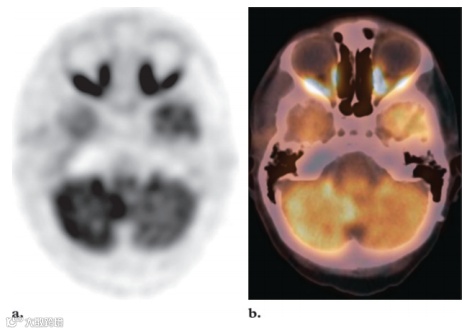

最强烈的FDG活性存在于正常的大脑皮层和基底神经节中,因为大脑依赖糖酵解代谢作为能量来源(图1)。大脑代谢可能占整个空腹状态下的身体代谢的20%。大脑的总吸收量约为注射剂量的FDG的6%。由于韦氏环淋巴组织的生理活动,腺样体、扁桃体和舌根通常会出现轻度至中度的摄取。然而,在韦氏环中可以看到明显的强烈摄取(图2),尤其是在儿童中,因为这些淋巴组织的生理活性很高,在6-8岁达到峰值,此后逐渐减弱。在儿童体内这些区域的正常FDG摄取并不一定意味着有疾病。通常情况下,生理性扁桃体和腺样体摄取的对称模式有助于识别这种正常变化。软腭也可显示强烈的放射性示踪剂摄取。唾液腺的摄取情况各不相同,但通常为轻度至中度(图3)。有研究报告称,约51%的患者腮腺有轻度至中度摄取,腮腺高度摄取约14%。颌下腺和舌下腺的摄取情况各不相同,阳性率分别为53%和72%。化疗或放射治疗后也可见唾液腺摄取量弥漫性增加。由于近期手术或放射治疗后出现急性炎症,唾液腺对FDG的摄取可能不对称。然而,放射治疗最终可能导致患侧摄取减少。

图2. 最大强度投影 (MIP) FDG PET 图像 (a) 和横向FDG PET (b)、CT (c) 和融合PET/CT (d) 图像显示正常扁桃体中有明显且对称的摄取 (箭头) 以及腮腺中有双侧轻度摄取 (b-d中的箭头) 。